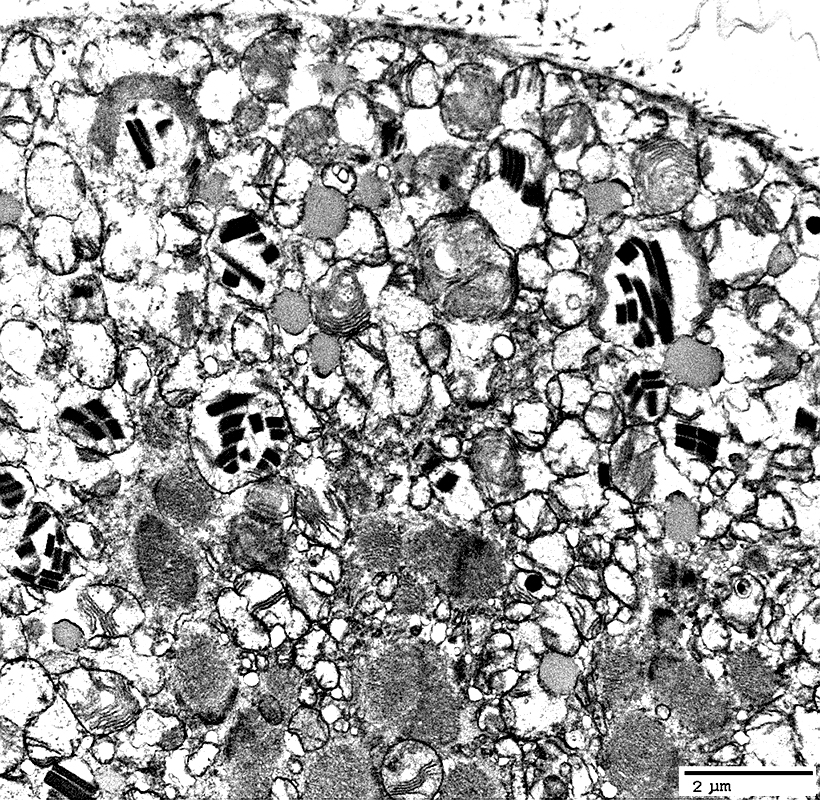

MNGIE: Muscle Ultrastructure

From: R Schmidt